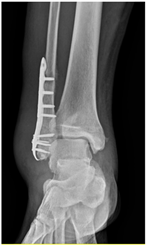

Patient A was a 70-year-old female with a right distal tibiofibular fracture and underwent ORIF in March 2020. There were no known comorbidities for Patient A. One year after ORIF, she began to develop recurrent bullae formation of the right foot, accompanied by tenderness around her operative wound. Neuromuscular function and range of motion were intact, but a local skin rash and bullae formation with hyperpigmentation were observed. The white blood cell count was within the normal range at 3739/μL, which reduced the possibility of FRI. A biopsy of the skin lesion from Patient A was evaluated for pathological examination (Figure 1). The lesion showed psoriasiform dermatitis changes. The epidermis demonstrated acanthosis, hyperkeratosis, parakeratosis, and spongiosis. There were alternating zones of hypo- and hypergranulosis, elongation of rete ridges, and thinning of suprapapillary plates. Neutrophils and lymphocytes infiltrated the epidermis and around blood vessels in the dermis, but eosinophils were rarely seen, which was less typical of an allergic reaction. However, delayed-type hypersensitivity (type IV) was suggested given the chronic 2-year course, manifestations without pus or highly elevated white blood cell counts, and a biopsy-proven predominant presence of neutrophils and lymphocytes. A topical corticosteroid was prescribed to manage the symptoms, but only a slight improvement was observed. Based on her medical history, as well as physical and pathological examinations, a diagnosis of contact dermatitis due to suspected hypersensitivity to the titanium alloy in osteosynthesis was suggested. Radiographs showed bone unions, and fixation with the titanium alloy was no longer necessary. Therefore, she underwent plate and screw removal in March 2023. The symptoms of allergy were resolved after implant removal following confirmed bone unions.

2.2. Case 2

Patient B was a 60-year-old male with a right distal fibular fracture and underwent ORIF in October 2019. His medical history included diabetes mellitus, hypertension, chronic kidney disease stage 2, and benign prostatic hyperplasia under regular medical control. He developed continuous painless right lateral ankle swelling of the right ankle for 6 months after the ORIF. His physical examination showed a local skin rash with progressive hyperpigmentation and hyperkeratosis around the operative site and local lymph edema at the right ankle. No fever, pus formation, or other specific signs were noted, and the white blood cell count of 8690/μL was also within the normal range before the removal of the implant. Accordingly, FRI was considered less likely, and an impression of hypersensitivity to the titanium plate was suspected. Radiographs confirmed bone unions over the right distal fibula. Under the impression of a chronic allergic reaction to the plates, he underwent the removal of the implants 6 months after ORIF. During surgery, screw loosening was noted, which may be related to chronic inflammatory reactions. The allergic manifestations resolved after the removal of the implants.